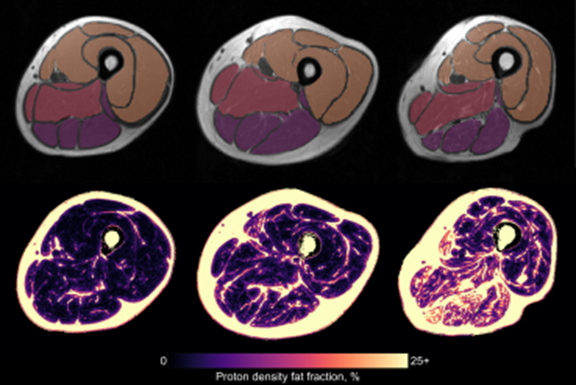

The technology measures musculoskeletal structures from rapid MRI scan protocols and produces 3D visualizations of muscle health, including individual muscle volume, left-right muscle asymmetry, bone volume, and intramuscular fat percentage, the company said.